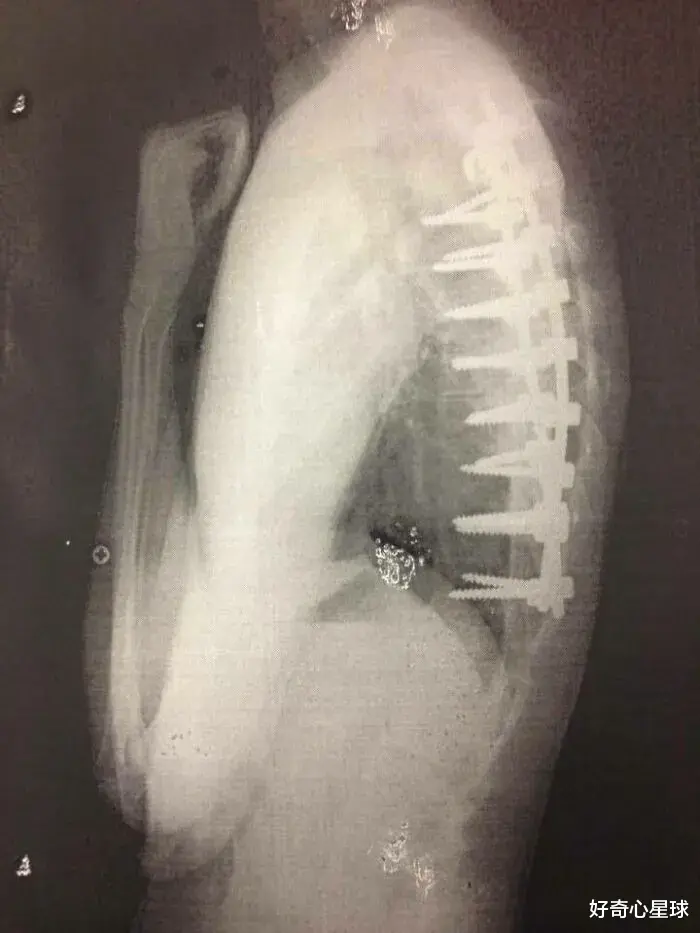

接受脊柱融合手术的患者。